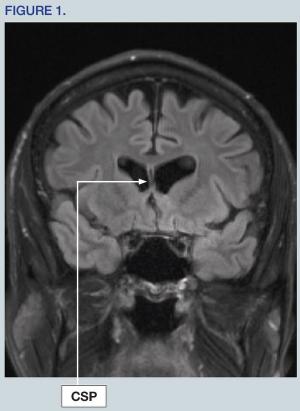

A 59-year-old man with a history of multiple concussions has been having a series of neurocognitive symptoms for the past several years. Discover more in this case.